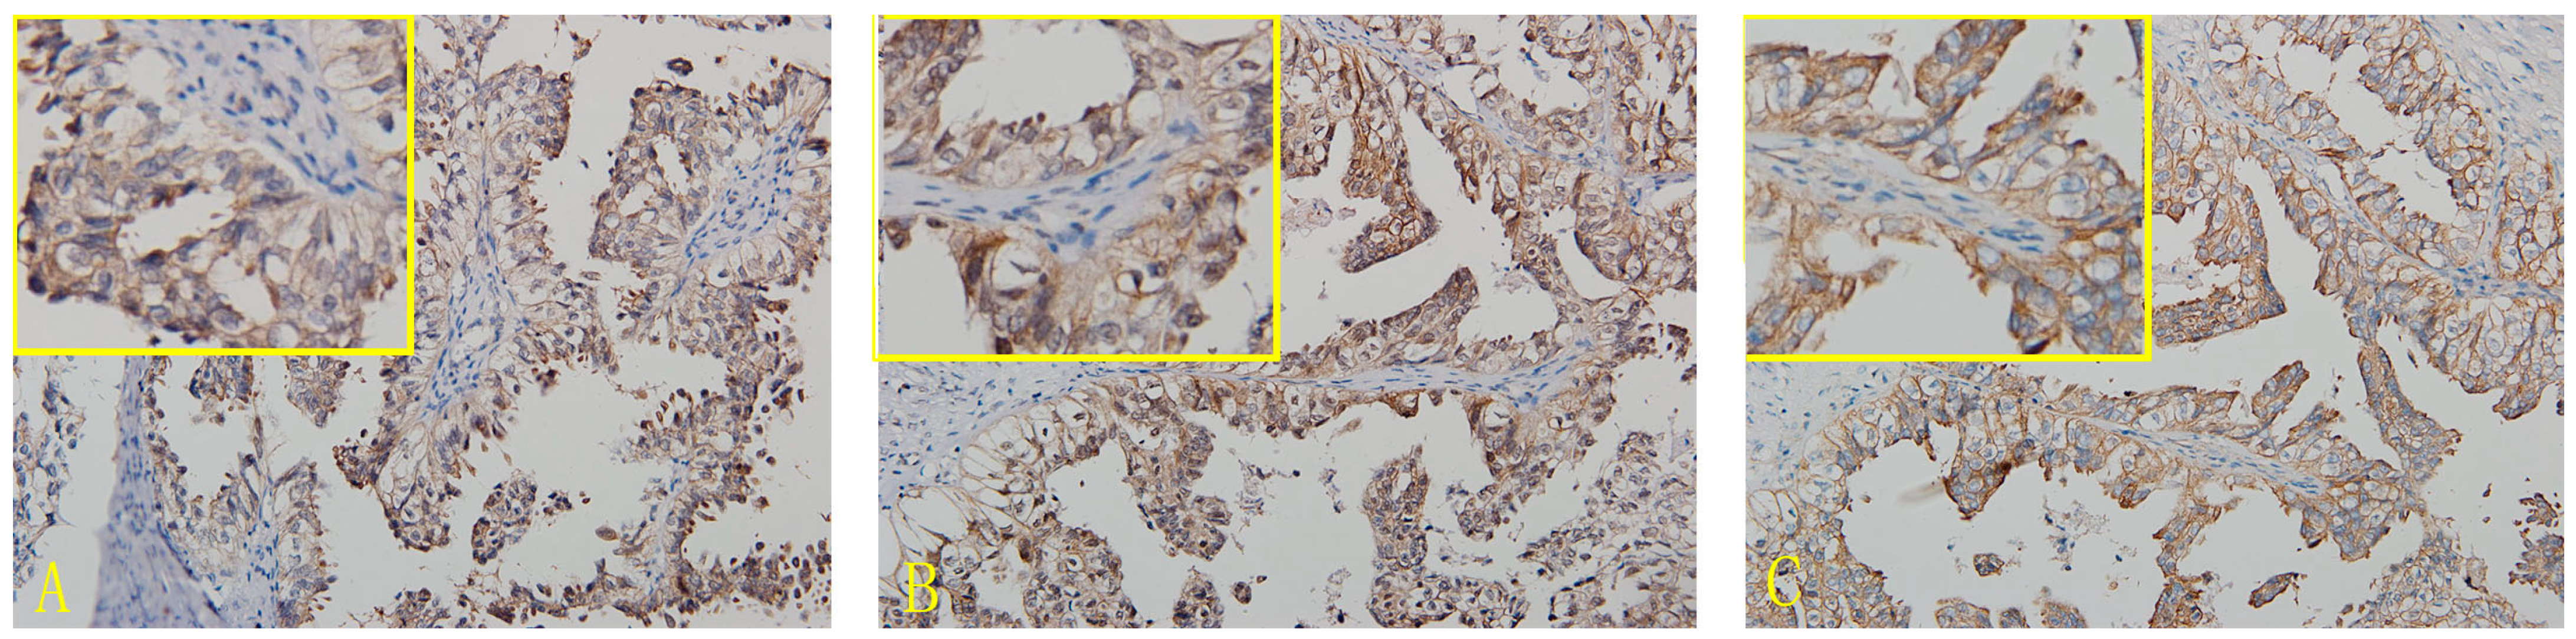

2.1. Expression of CD44, CD47 and c-met in OCCC

4.2.1. Immunohistochemistry

4.2.2. Assessment Standard